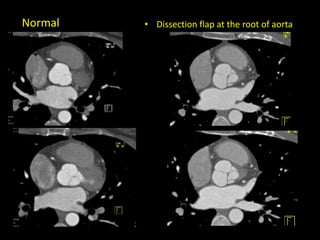

• Dissection flap at the root of aortaNormal

• Dissection flapat the root of aortaNormal